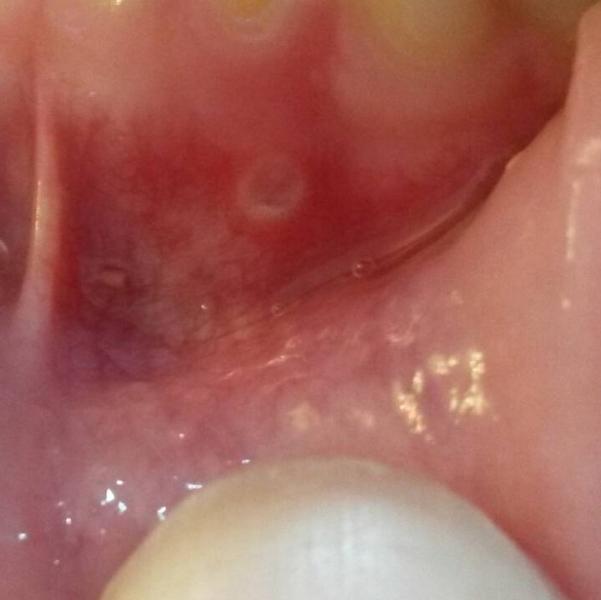

Девочки, может среди нас есть стоматологи. У дочки 5 лет на нижней десне появилась болячечка и она ей болит. Что это? Может стоматит? Чем лечить? Извините за не очень эстетичное фото.

Похоже на афтозный стоматит. У старшего сына иногда бывает. Солкосерил дентальная мазь очень помогает(это единственное, что помогает) Буквально за два дня все проходит.

У нас помню такая точка была от того,что доченька хлебанула горячего компота! ожог!